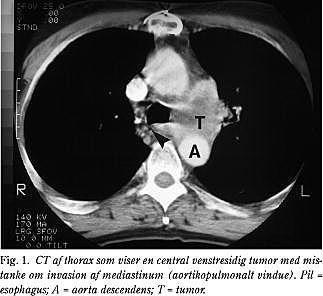

Materialet omfatter 84 patienter henvist til thoraxkirurgisk afdeling, Amtssygehuset i Gentofte, i perioden 1.4.1993 til 31.12.1999 med henblik på vurdering af esophagusnære malignitetssuspekte mediastinale forandringer påvist ved CT (Fig. 1 ). Der var 36 kvinder og 48 mænd med en median alder på 62 år (spændvidde 35-82 år).

EUL-FNA-undersøgelserne blev udført i sammedags-kirurgisk afsnit med patienten i let midazolamrus. Der blev anvendt et fleksibelt UL-endoskop med curved array transducer og justerbar UL-frekvens på 5 eller 7,5 MHz, (Pentax FG-32 UA, FG-34 UA og FG-36 UA). Til biopsi blev anvendt et biopsiinstrument med en 22 gauge nål (GIP/MEDI-Globe, type Hancke/Vilmann). Biopsierne blev foretaget transøsofagealt med 1-3 nålepunkturer per proces (Fig. 2 ) og udstrøget på objektglas med henblik på cytologisk vurdering.